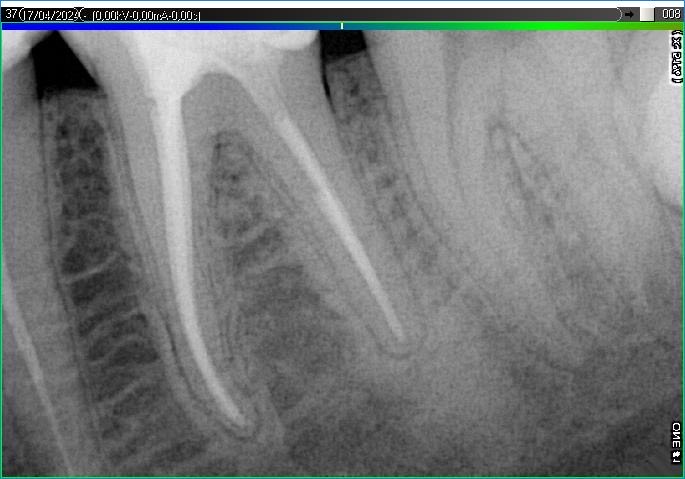

Вилучення інструменту з каналів зуба